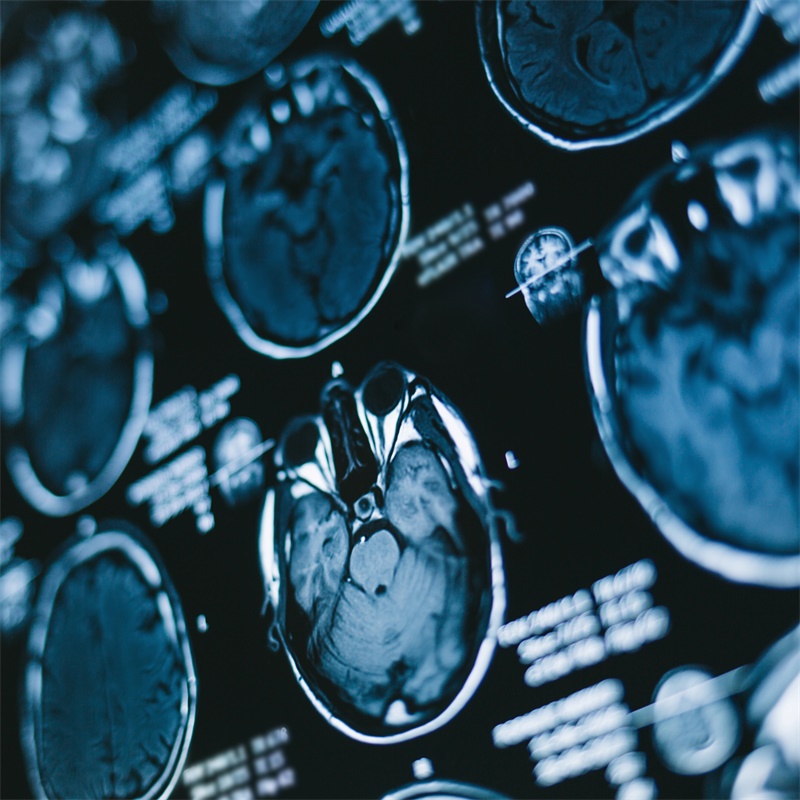

基本情况:32岁男性,表现为进行性头痛、复视(左眼完全复视,右眼一个月前部分复视)、右侧感觉障碍和步态障碍。神经学检查显示完全的左外展神经麻痹,整个右侧面部和身体的...